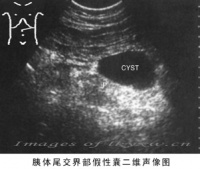

B超检查[编辑 | 编辑源代码]

B超检查是诊断胰假性囊肿的一项简便而有效的手段,典型者于上腹可探及一位置明确、范围肯定的液性暗区。B超对鉴别包块和囊肿特别有助,对胰假性囊肿的诊断正确率可达73%~91%。动态的超声探查可了解囊肿大小的改变。此外,在B超引导下,可作囊穿刺,抽取囊液作生化细胞学检查。